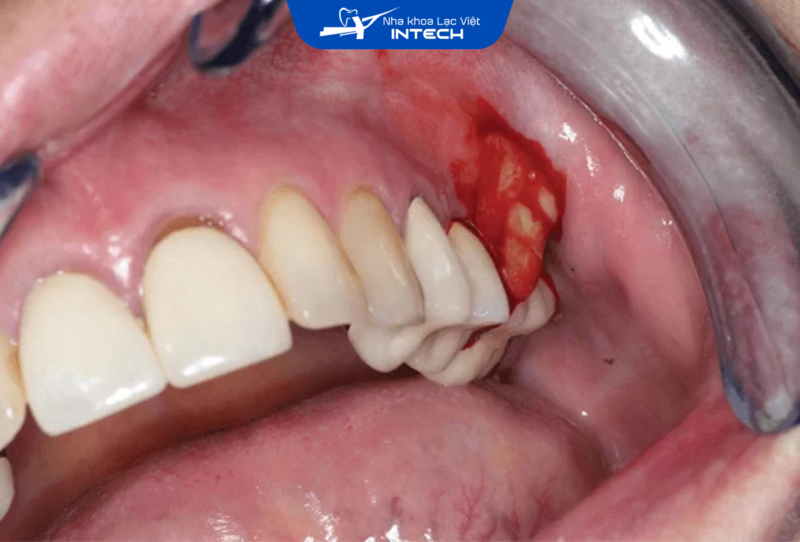

• Nạo vét các tổ chức viêm quanh chân răng Implant để loại bỏ hoàn toàn tác nhân gây viêm, đồng thời tái lập lại khả năng bám dính của nướu quanh Implant, giúp bảo vệ trụ Implant và mô mềm xung quanh.

• Nếu viêm nhiễm đã gây tổn thương nghiêm trọng, bác sĩ có thể thực hiện phẫu thuật để loại bỏ mô viêm, nạo vét túi nha chu, hoặc nâng nướu, ngăn chặn tình trạng viêm tiếp diễn.